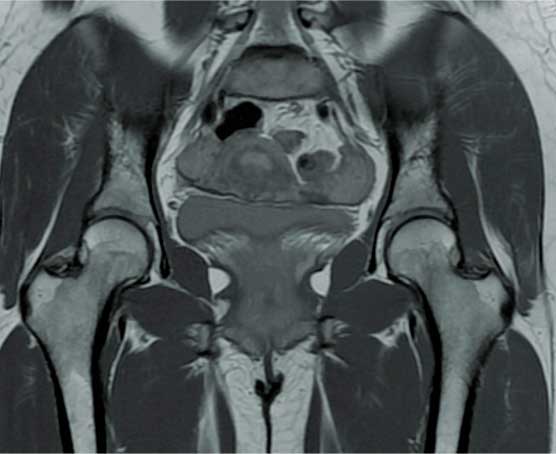

Artroscopia

de cadera

Cirugía mínima invasiva que se realiza haciendo tres puertos alrededor de la cadera por los cuales se introduce una cámara y observamos el interior de la articulación para buscar el daño o problema, también se introducen instrumentos con los cuales se permiten reparar las lesiones.

Está indicada en un paciente adulto joven para diagnosticar y tratar con certeza problemas de bloqueo en la cadera, extracción de cuerpos libres intrarticulares, rupturas de labrum, lesiones del cartílago y choque femoroacetabular.